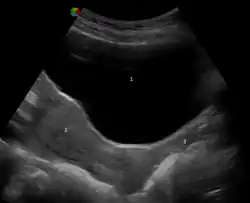

![]() Normal adult human vagina, before (left) and after (right) menopause | |